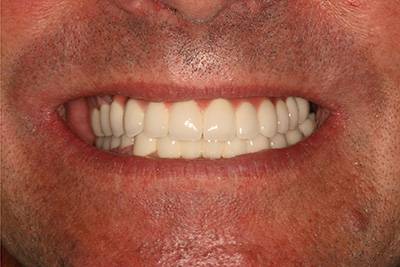

10. eset

Savas kémhatású anyagok, mint például a szénsavas üdítők túlzott használata is a fogak zománcrétegének nagyfokú károsodását okozhatják. 35 éves férfi páciensnek készítettünk a frontfogaira Zirkon koronákat, a rágófogaira pedig fémkerámia szóló koronákat. 28 koronával állítottuk helyre a fogazatot.